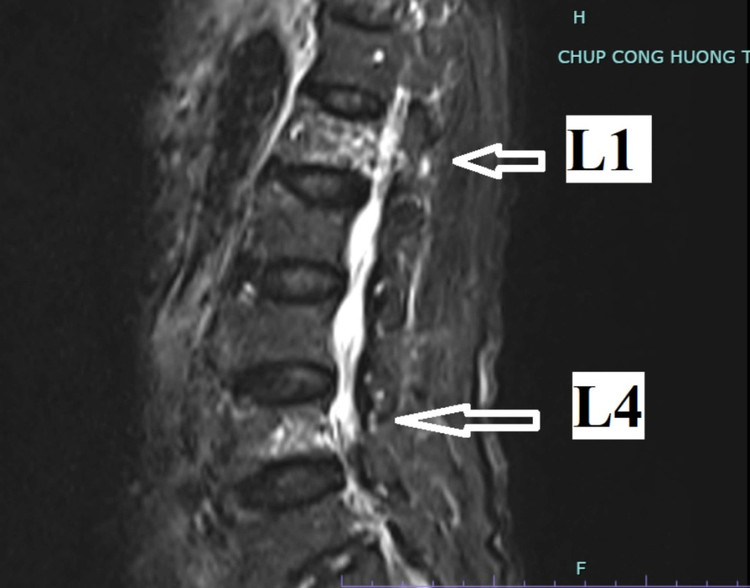

Qua thăm khám và thực hiện kiểm tra chuyên sâu, bác sĩ chẩn đoán người bệnh bị lún đốt sống L1, L4 sau ngã trên người bệnh loãng xương nặng. Người bệnh được chỉ định phẫu thuật bơm cement sinh học tạo hình thân đốt sống. Ca phẫu thuật bơm cement chỉ diễn ra trong 15 phút, người bệnh không phải gây mê toàn thân, chỉ cần gây tê tại chỗ.

| Hình ảnh phim chụp của người bệnh cho thấy bị lún đốt sống L1, L4 - Ảnh: BVCC |